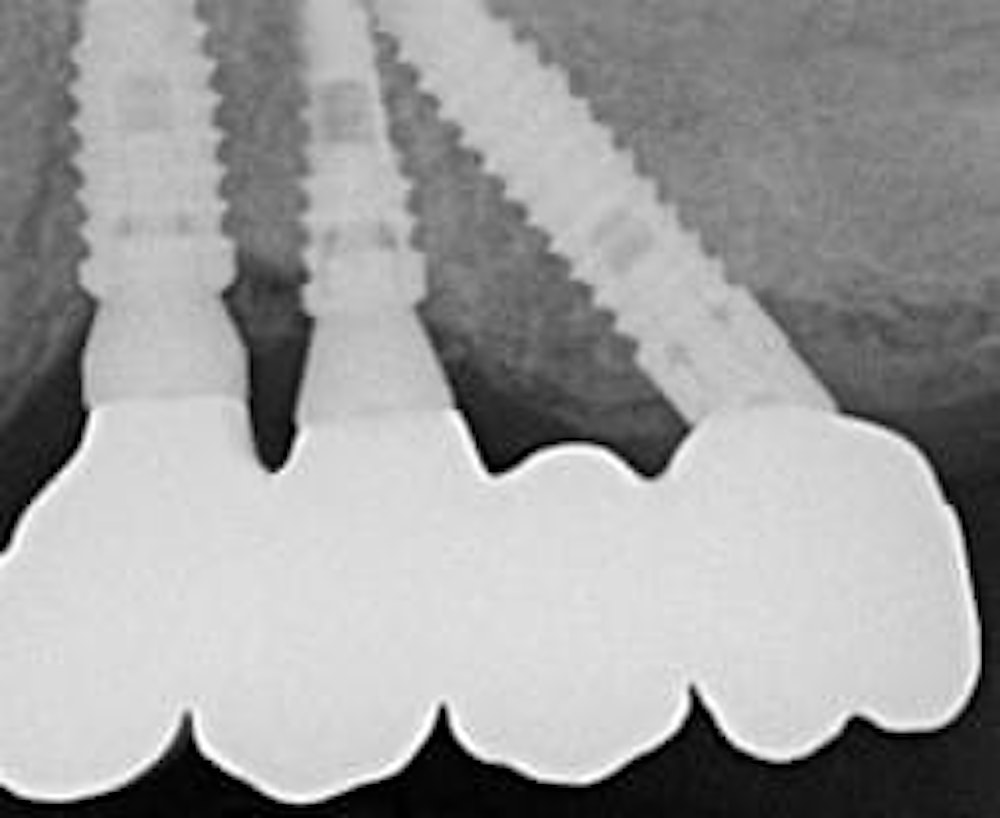

For moderate to severe maxillary atrophy, in the presence of surgically challenging sinus anatomy, the apex of the posterior implants can be angled anteriorly, passing transsinus, to apically fix at the lateral piriform rim into the lateral nasal wall. The most important bone for apical fixation of implants in this setting is the lateral nasal bone mass with the maximum available bone found at the piriform rim above the nasal fossa (4,5). This area, designated the M point, also can engage two implants placed at 30-degree angles (Figs. 1a-b). The transsinus implants are then grafted and possibly placed into immediate function, depending on the level of crestal stability present.

An incision is made along the crest with vertical releasing incisions to obtain access to the lateral and anterior walls of the sinus. The extension of the flap is smaller than a traditional sinus elevation. Once a full-thickness flap is elevated, a small antrostomy is made parallel to the anterior sinus wall starting 3 mm distal to it and then extending anteriorly to reach the anterior sinus wall. The antrostomy is usually 4 to 6 mm mesiodistally and 7 to 8 mm apicocoronally. This simplified antrostomy design is preferred because extension of the antrostomy to the anterior wall renders the membrane elevation procedure simpler and safer by providing direct visual access to the narrow anterior portion of the sinus. This results in a reduced membrane perforation rate (Fig 2a-b).

Distal displacement of the sinus membrane allows for the placement of an implant with a distal tilt of 30 degrees (Fig. 3). The direction of the first implant drill can be observed through the antrostomy. The preparation of the implant site extends apically through the anterior sinus wall into the cortical layer of the often adjoining lateral nasal wall. After verification of the implant axis using direction indicators, the drilling sequence is finalized and a bone substitute is inserted (on average, 1 mL of graft material is needed). The implant is then inserted through the residual crestal bone into the grafted sinus where the membrane has been previously displaced distally. It engages apically at the M point, the confluence of three cortical walls. In some cases, it may be possible to obtain satisfactory implant stability without engaging the lateral nasal wall cortex. This approach further simplifies the surgical procedure.

Many studies have emphasized that bone density is an important factor for implant success (6,7). The technique proposed in this article targets implant stabilization in three layers of cortical bone: the cortical layer at the osseous crest of the alveolar process, the cortical layer at the floor of the maxillary sinus, and the cortical layer of the anterior sinus wall.